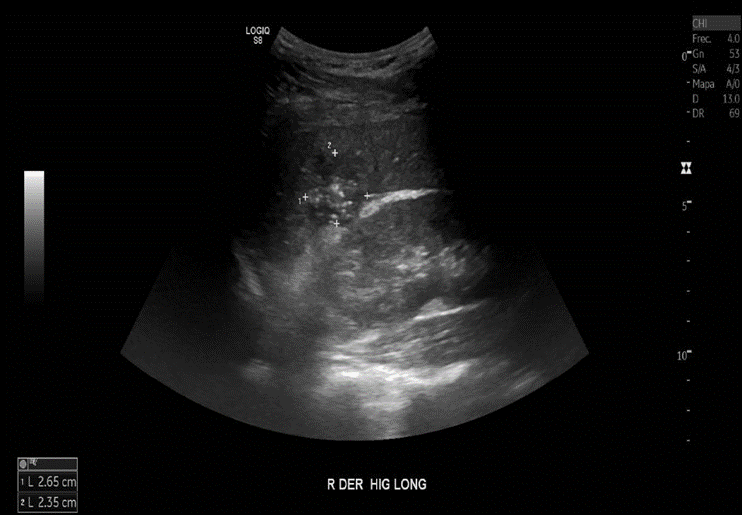

Incidentalmente se observa nódulo hepático en lóbulo derecho, hipoecogénico, mal delimitado, escasamente vascularizado asociado a calcificaciones puntiformes en su interior que protruye levemente hacia la cápsula hepática, inespecífico. Podría corresponder a un proceso inflamatorio.

Incidentalmente, se observa lesión focal hipoecogénica con múltiples focos puntiformes ecogénicos en el lóbulo hepático derecho, mide aproximadamente 33 mm de diámetro mayor.

Lesión focal hepática derecha incidental. Se sugiere caracterizar mediante examen axial contrastado, de preferencia Resonancia Magnética.